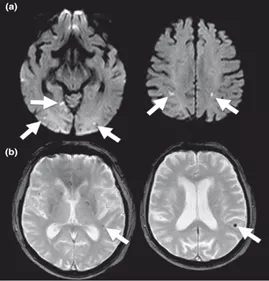

腦澱粉樣血管病相關炎症(CAA-ri)通常認為是軟腦膜及腦血管β-澱粉樣蛋白引起的炎症反應。典型的CAA-ri MRI表現為單灶或多灶不對稱白質高訊號(WMH)病變(皮質下或深部)延伸至皮質下白質,並伴有CAA相關出血併發症。通常在相關WMH附近觀察到大量的CMBs(圖1)。

圖1 CAA患者的T2WI(a-d)和FLAIR(e),可見皮質下微出血(a-c,白色箭頭)、亞急性晚期腦葉出血(c和e,黑色箭頭)、皮質鐵沉積(c和d,箭頭)、皮質下腦白質高訊號(WMH,e)、腦葉血管周圍間隙擴大(EPVS,e,箭頭)。